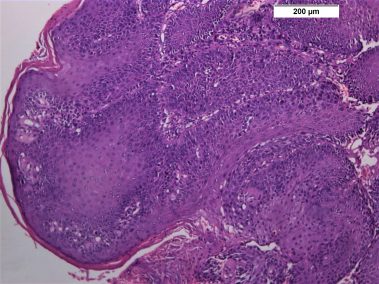

85 years old male came to the clinic suffering from painful ulcer in the left buccal mucosa related to the lower first and second molars. The patient stated that this ulcer appeared three months ago and was preceded by long standing reddish white lesion. The related molars have grade 3 mobility upon clinical examination.